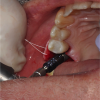

The patient wanted an implant-supported crown to restore the right mandibular first molar, which had been extracted after recurrent caries, endodontic treatment, and development of a periapical lesion. The site was grafted with bone grafting material and a biological membrane and allowed to heal for 6 months. A periapical radiograph was then taken (Figure 6), which showed the socket areas to be well condensed, with mature-looking bone. A CBCT scan was taken to facilitate implant-placement planning.

Fig 6. Periapical radiograph, single missing tooth.

Figure 6